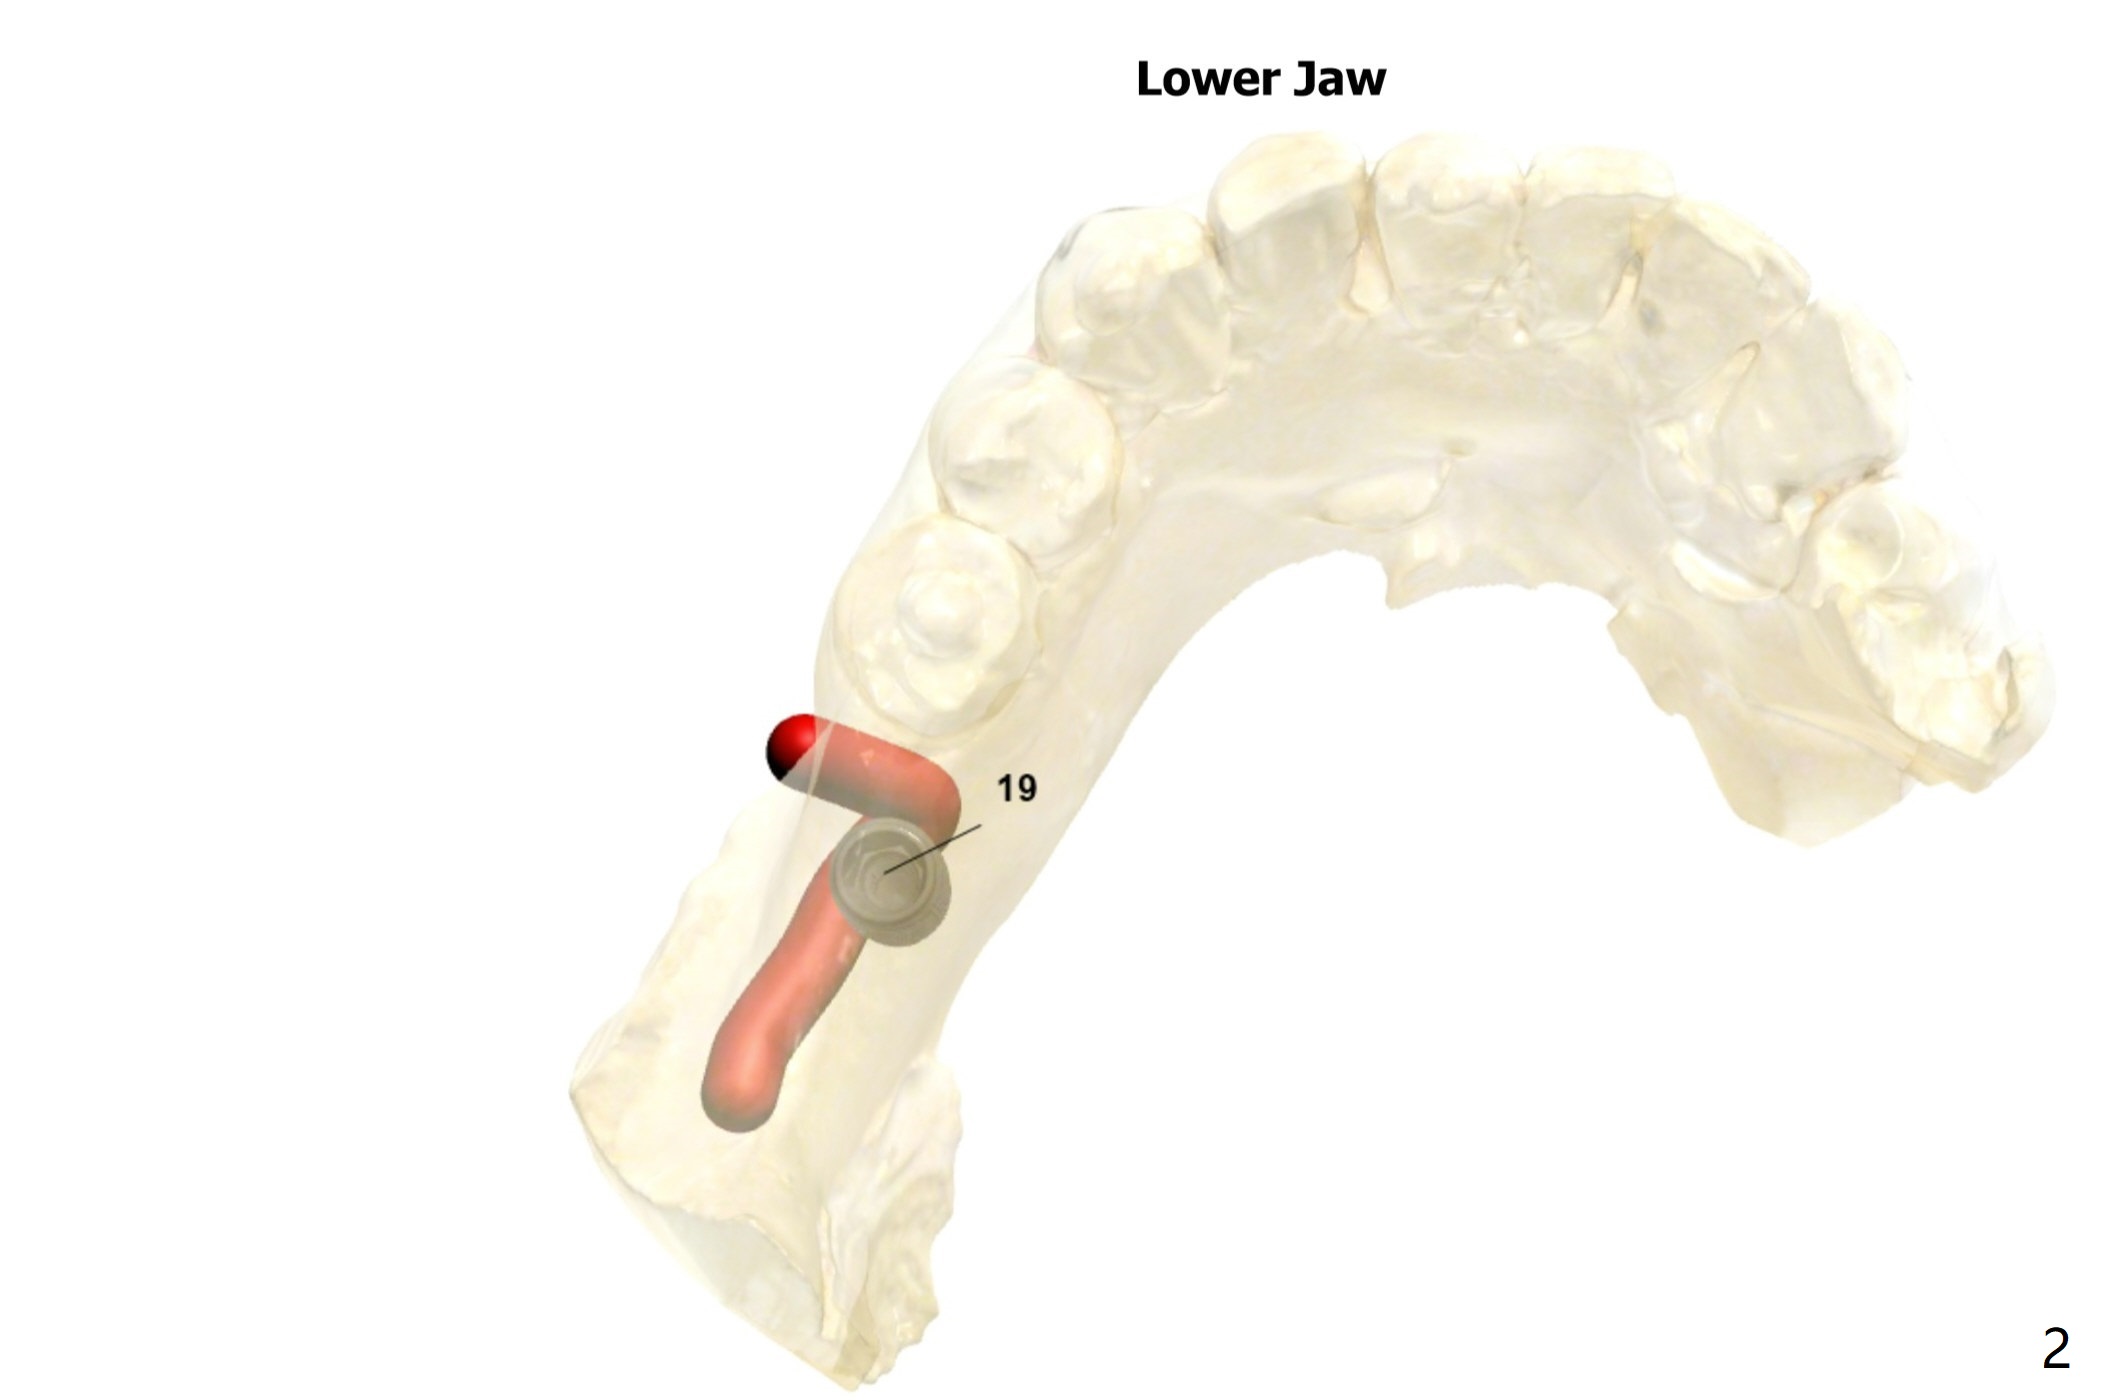

Bone Expansion through Guide

A 53-year-old woman requests implant at #19 after redo #14 crown. The ridge is narrow (holding a 3.5x11.5 mm implant) and apparently low in density (Fig.1). Bone expansion seems necessary. Following use of 2.2 mm drill to the depth, bone expanders will be introduced (1.7/3.1 and 2.4/3.7 mm). After 4.0 mm cortical tap, a 4.0x11.5 mm implant is placed. If torque is high, use 3.5 mm drill. Postop 5x5 cm CT will be taken. Also take pre- and post-op photos of the buccal plate. Prepare surgical handpiece and a new thin fissure bur for ridge split as well as split saw block. Use a UF implant, in consistent with that at #11.